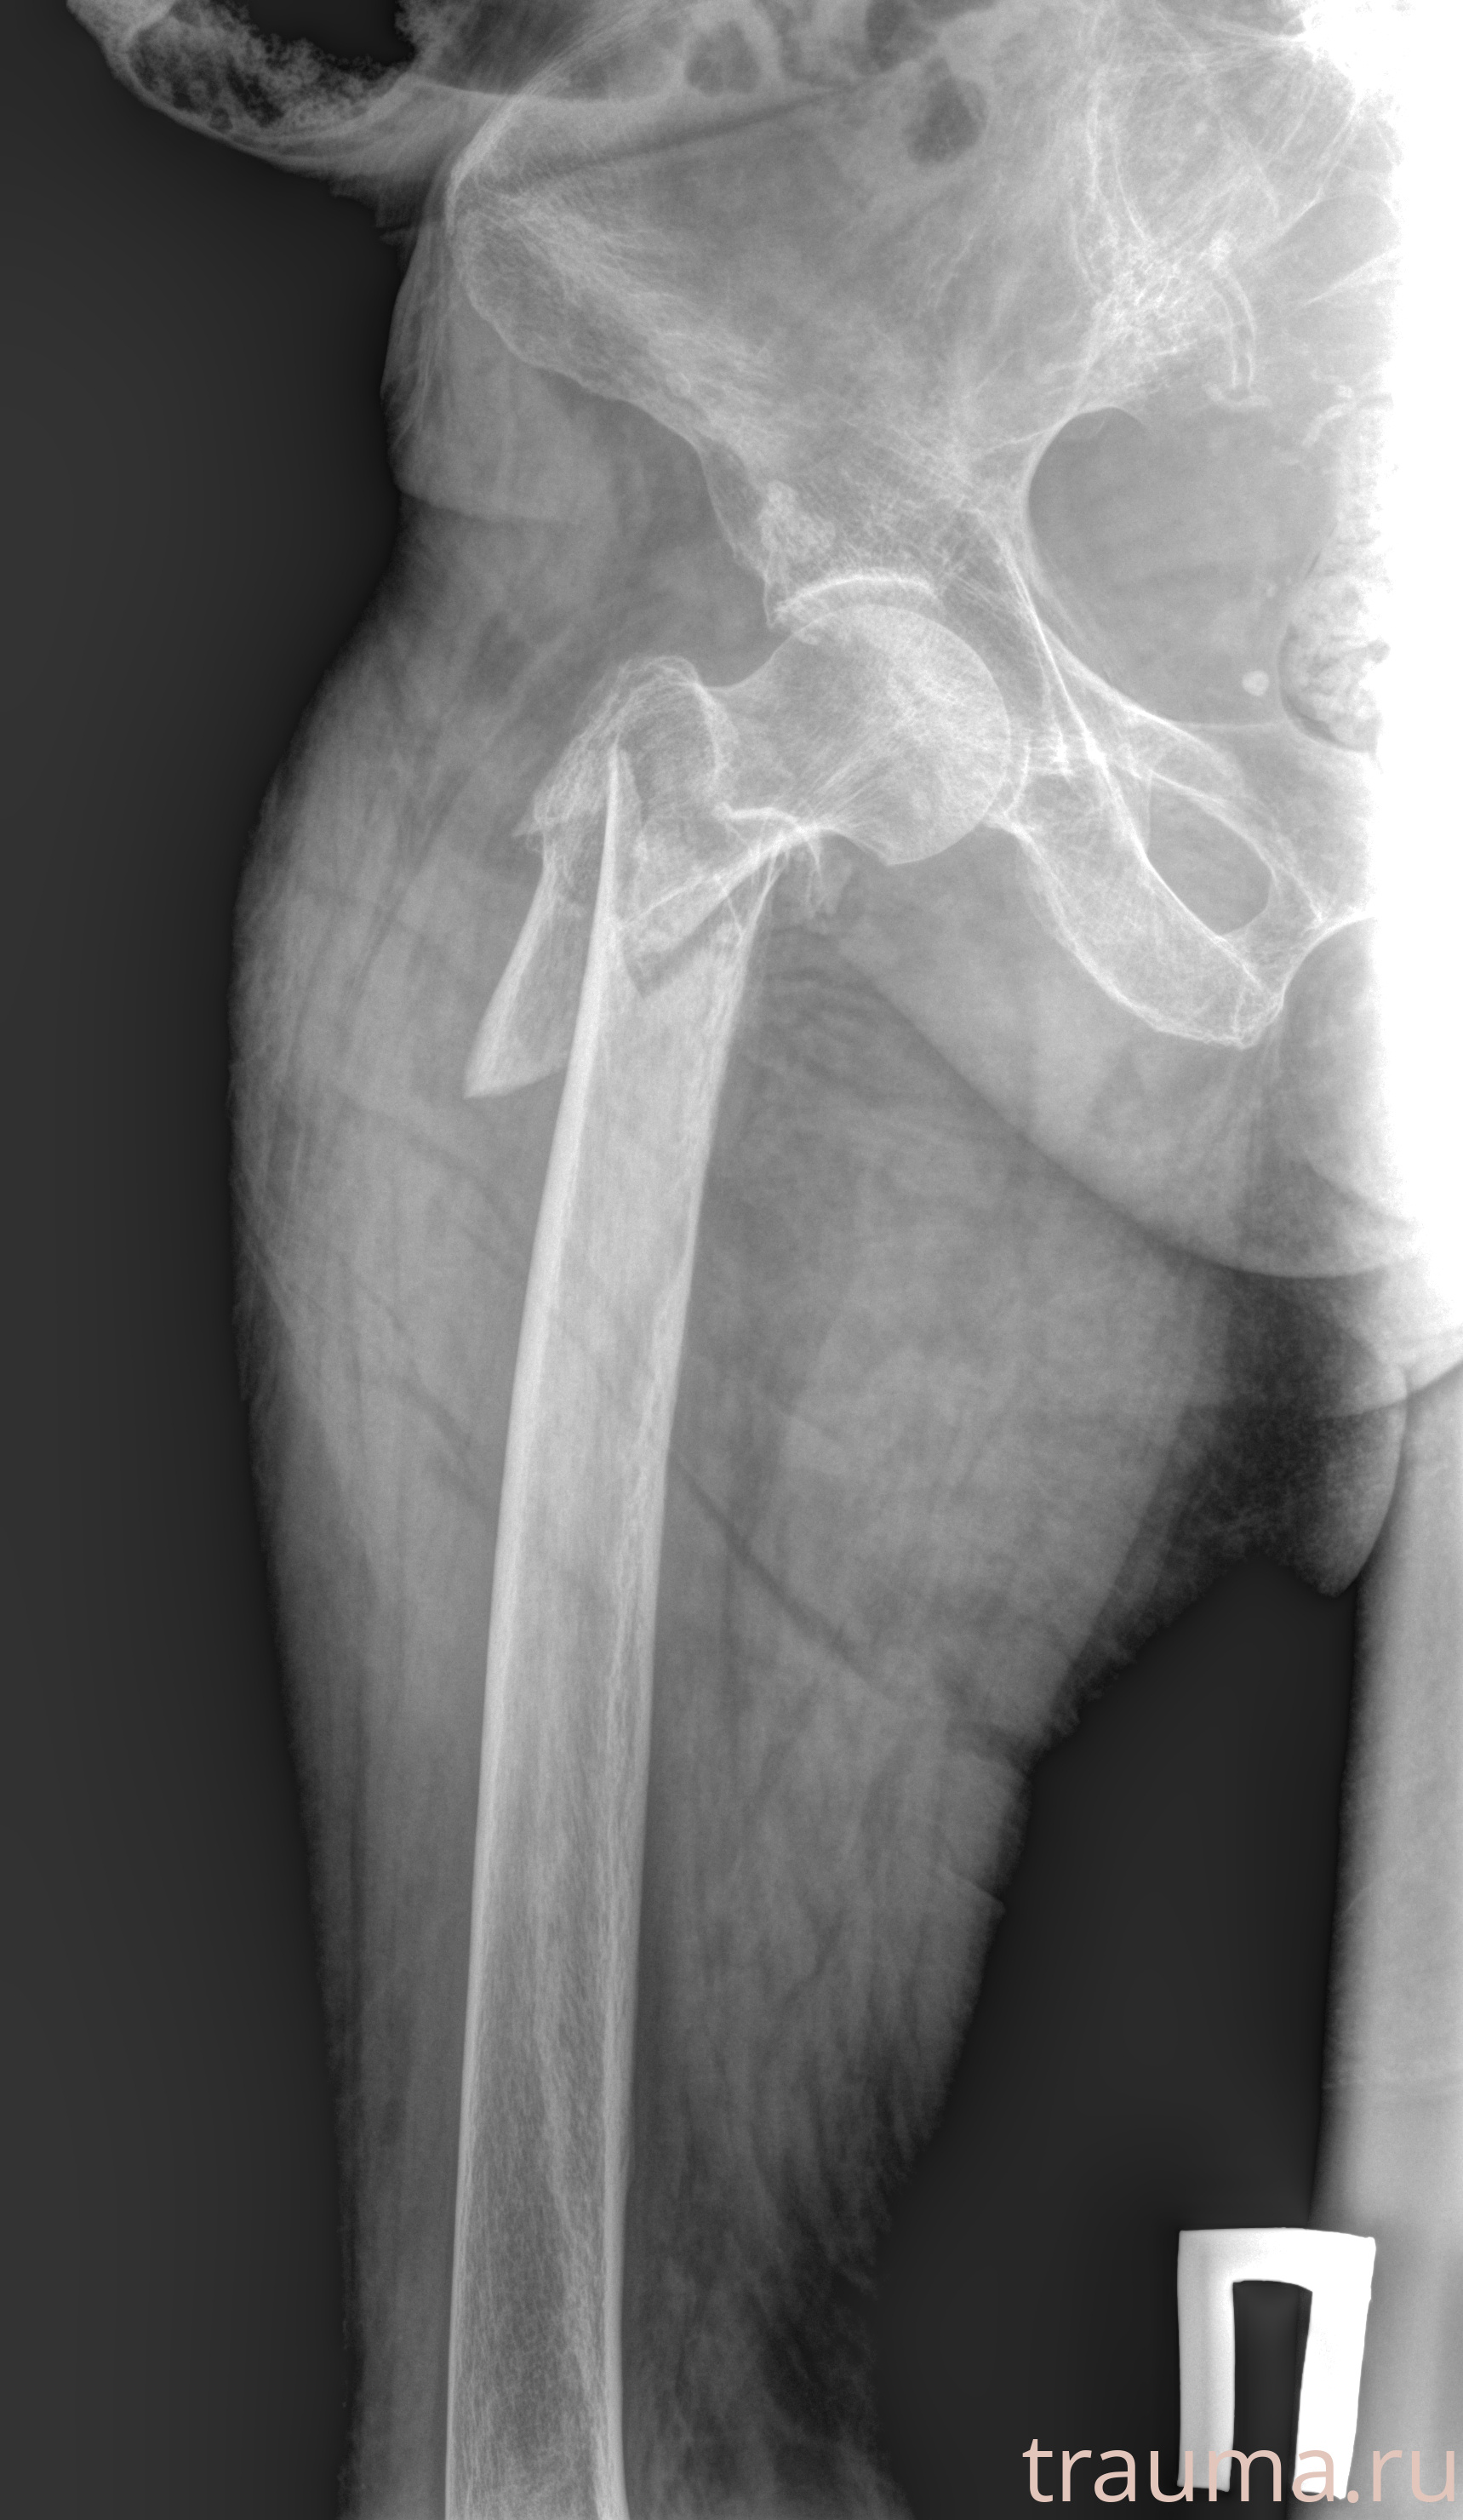

Рентгенограммы

Рентген на дому: по вашему адресу приезжает врач-рентгенолог, травматолог-ортопед с мобильным рентгеновским аппаратом, проводит диагностику травмы или заболевания, делает необходимые рентгенограммы, дает рекомендации по дальнейшему лечению. Получить качественные снимки в домашних условиях возможно благодаря уникальной методике, разработанной МосРентген Центром для института  Склифосовского